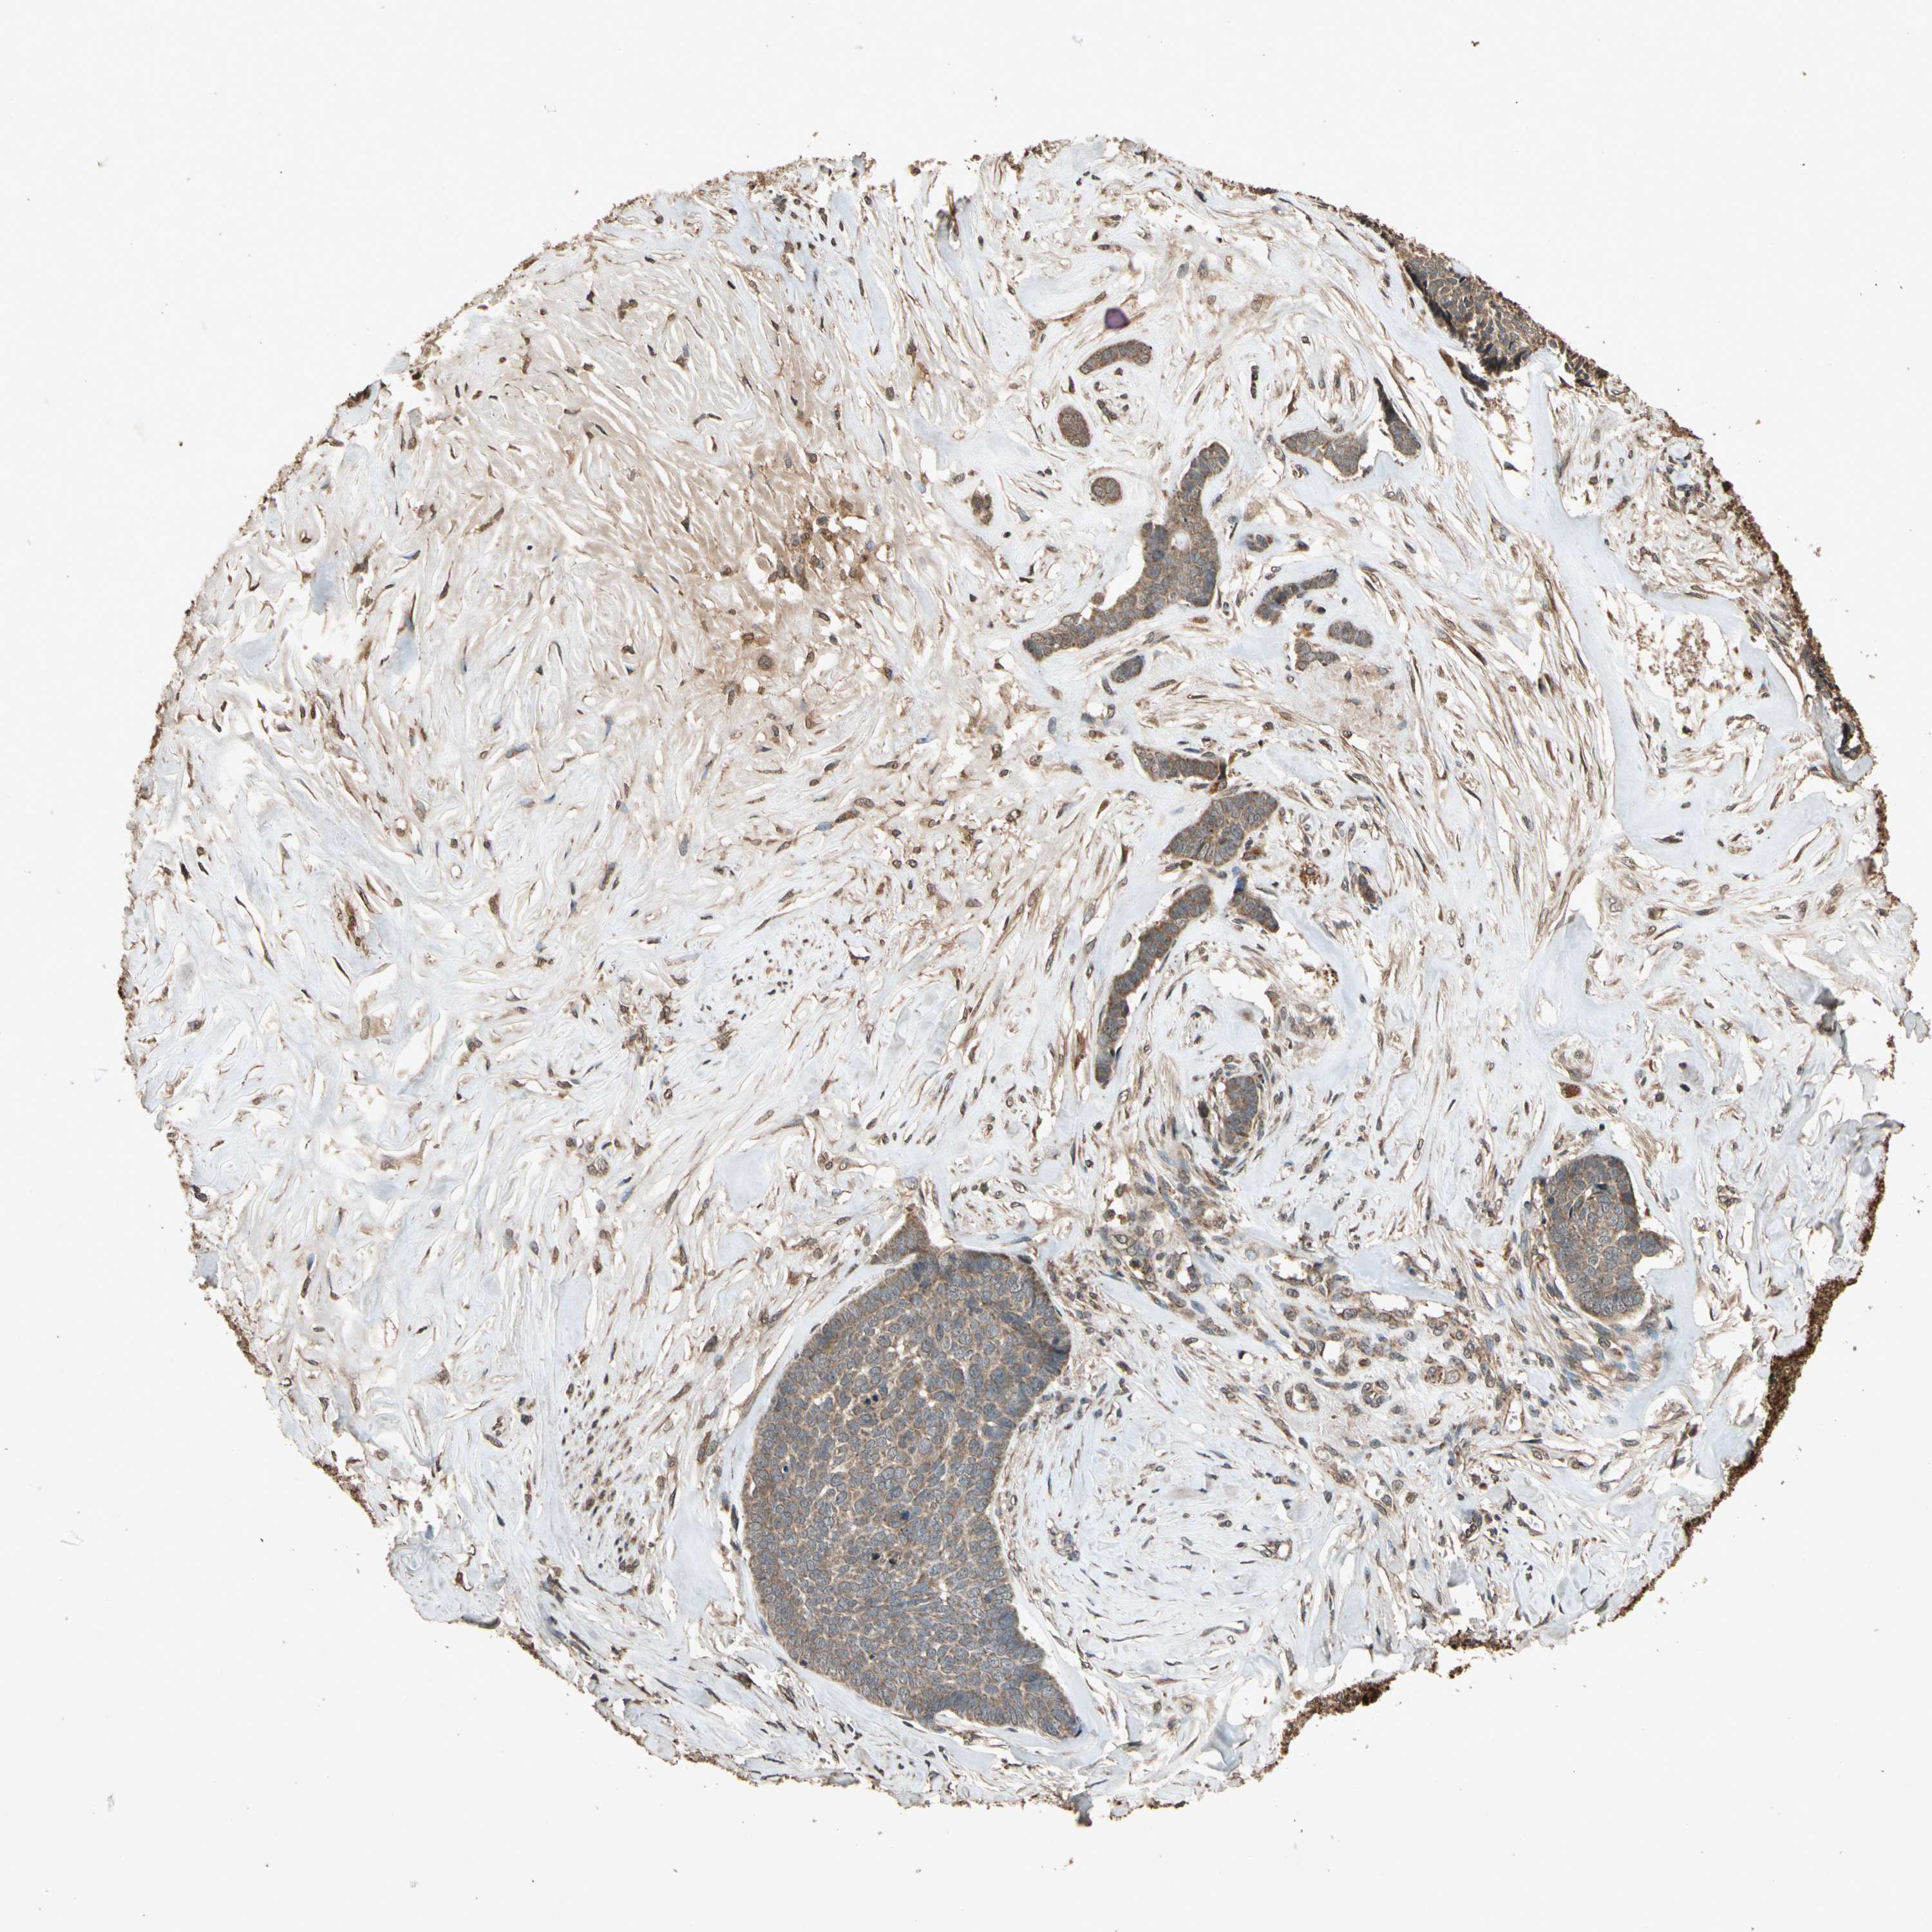

SKIN CANCER - Protein expressioni

A mouse-over function shows sample information and annotation data. Click on an image to view it in a full screen mode. Samples can be filtered based on level of antibody staining by selecting one or several of the following categories: high, medium, low and not detected. The assay and annotation is described here.

Antibody stainingi

Antibody staining in the annotated cell types in the current human tissue is reported as not detected, low, medium, or high, based on conventional immunohistochemistry profiling in selected tissues. This score is based on the combination of the staining intensity and fraction of stained cells.

Each image is clickable and will lead to virtual microscopy that enables deeper exploration of all samples and also displays staining intensity scores, fraction scores and subcellular localization as well as patient and tissue information for each sample.

Antibody HPA000994

Antibody CAB008681

Staining

Intensity

Strong

Quantity

>75%

Location

Nuclear

Squamous cell carcinoma, NOS

Basal cell carcinoma